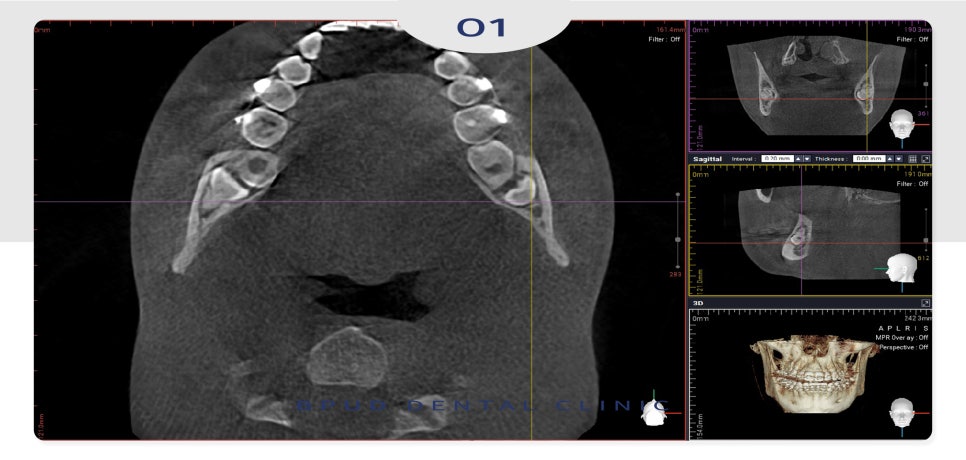

24.12.03

완전 매복 고난이도 사랑니로

신경에 완전히 닿아 있어 신경 손상의

위험이 높은 케이스였으나 문제없이

발치 계획을 수립하였습니다.

이처럼 정상적인 발치를 할 수 없는

위치에 치아가 있는 경우 발치 시

어려움이 있기 때문에

3D CT 촬영을 통해 정밀한 진단을

바탕으로 치아 상태를 입체적으로 파악하여

계획을 세워야 부작용의 위험을 줄일 수 있습니다.